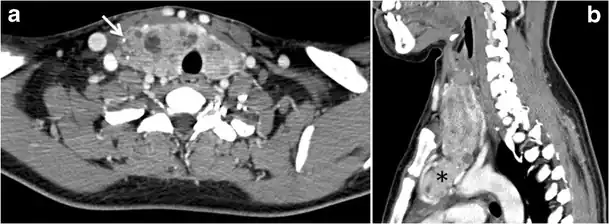

Fig. 13. A 27-year-old female patient known to have goiter. a, b Axial and sagittal enhanced CT scan images of the neck demonstrate a heterogeneously enhancing, enlarged thyroid gland with scattered calcifications (white arrow), cystic changes, and substantial retro-sternal extension (black asterisks). No lymphadenopathy or substantial airway narrowing.[1] -

Malignancy can coexist within the goiter and a CT scan may give a clue if there are abnormal cervical lymph nodes and/or signs of invasion. Retrosternal extension (Fig. 15) could affect the surgical approach, as a lower extent may require a partial or total sternotomy to facilitate complete resection. Therefore, the distance of the retrosternal extent from the sternal notch should be measured on a sagittal image.[1]